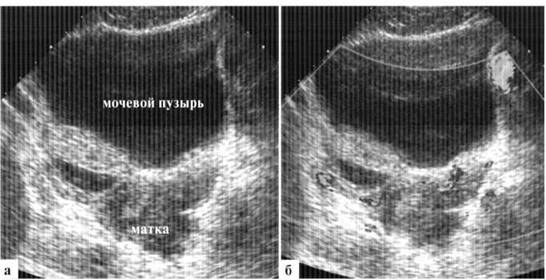

Матка новорожденной может достигать размеров 20 (длина)х2() (ширина)х15 (толщина) мм с толщиной М-эха до 5 мм. Неонатологам хорошо известны клинические проявления так называемого «полового криза» новорожденных, в том числе и кровянистых выделений из влагалища. Такие особенности строение внутренних гениталий также связаны с гормональным фоном ребенка, особенностями гормонального фона матери, наличием или отсутствием грудного вскармливания. В норме у новорожденной девочки шеечно-маточный угол не выражен, толщина тела и шейки матки практически одинаковая и граница между ними видна нечетко, соотношение длины тела матки к шейке — около 1:2 (рис. 1.3).

Рис. 1.3. Матка здоровой новорожденной (контур обведен пунктиром): а — фронтальный скан; б— сагиттальный скан